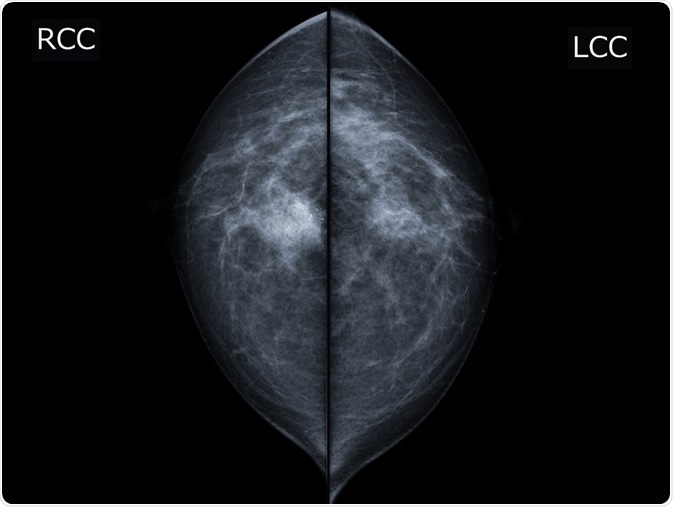

X-ray mammogram image of breast with cancer. - breast cancer of right breast. Image Credit: MossStudio / Shutterstock